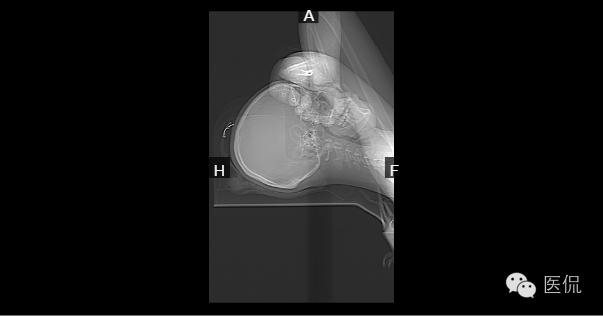

检查方法:L3--S1椎间盘平扫

胸腰段生理性曲度以L1、2为中心后突,L1~椎体前缘见椎缘骨,各椎间隙未见明显狭窄;横断位:L4-5、L5-S1椎间盘朝后突出,相应硬膜囊前缘受压;黄韧带不增厚;L5-S1右侧椎间小关节面增生、硬化,间隙狭窄,椎旁软组织未见异常。

1、腰椎生理曲度后突。

2、L4-5、L5-S1椎间盘突出(后中央型)。